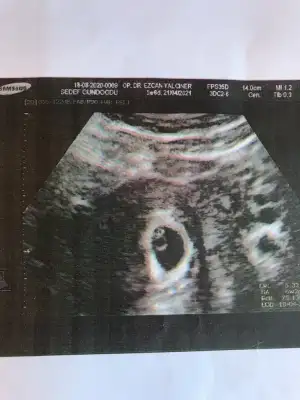

Keseyi gördüm çok şükür🙏

Ama başka bişey göremedik henüz. 10 gün sonraya tekrar çağırdı kalp atışı için.

En azından dış gebelik ihtimali kalktı :KK51: Ama yine de 10 gün nasıl sabredeceğim bilmiyorum